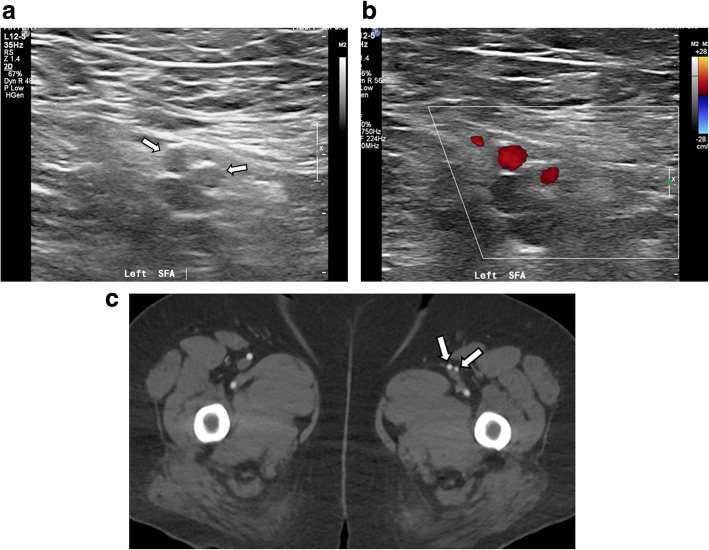

Fig. 1.

Gray scale (a) and color Doppler ultrasonography (b) show that the left superficial femoral artery is divided into two trunks (arrows) with similar luminal diameter and courses parallel. The axial image of arterial phase CTA of bilateral lower extremity (c) shows the duplicated left superficial femoral artery (arrows). The luminal diameter of the medial one is slightly larger than that of the lateral one. Note normal right superficial femoral artery

The patient underwent Doppler US examination on bilateral lower extremity arteries and veins to examine potential vascular abnormality. There was no abnormality in vessels of the right side. The left SFA was revealed to be divided into two trunks with similar luminal diameter and courses parallel (Fig. 1). They reunited at distal thigh level. No other abnormalities or diseases in vessels of the left side were identified by US examination.

For further evaluation, CTA of bilateral lower extremities was performed. The left SFA appeared to originate from left common femoral artery at the same level of the contralateral side. It appeared to run as a single vessel, 4 cm long, then split into two branches, medial and lateral ones. The luminal diameter of the medial one of the SFA was 5.3 mm, whereas that of lateral one was 4.4 mm, measured in each proximal portion (Fig. 1). Both then traveled 14 cm distal along anterior side of the left superficial femoral vein. They merged at distal thigh level to form single vessel and ran 4 cm distal to enter the adductor hiatus. The anatomic orientation was well visualized in three-dimensional volume rendering and maximum intensity projection images (Fig. 2). There was no evidence of atherosclerotic stenosis or other diseases on the bilateral lower extremity arteries. The findings of US and CTA examination did not correspond with the symptom of the patient, and the patient was discharged.